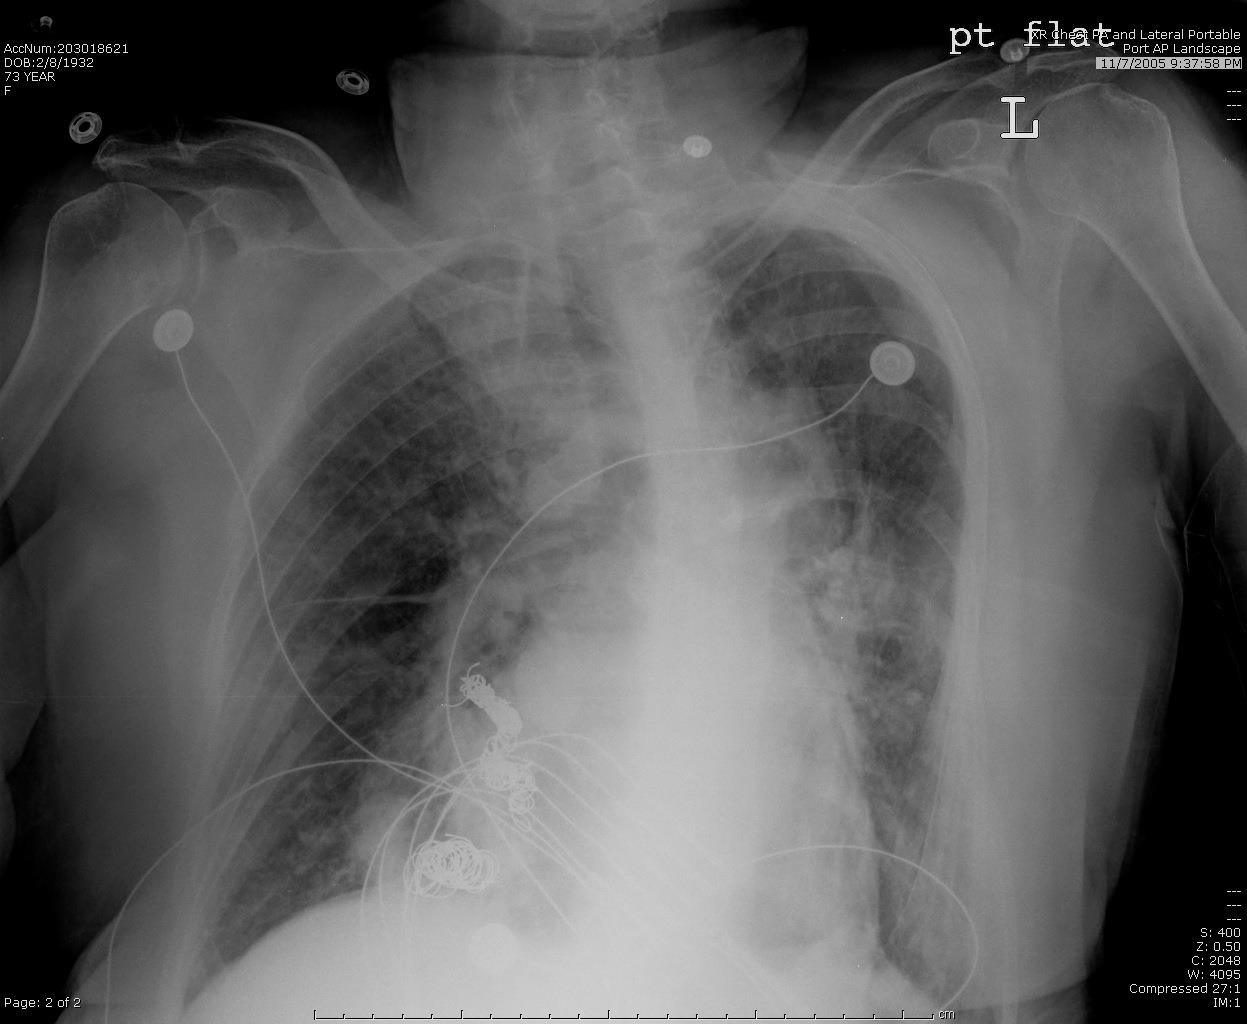

栓塞后弹簧栓子逸出至右肺静脉 |

栓塞后弹簧栓子逸出至右肺静脉 |

|

|

|

|

|

弹簧栓子在左心房“狂”跳 |

没啦? |

|

|

|

|

去哪儿啦? |

在这儿! |

造影 |

|

|

|

|

嵌在股深浅动脉分叉处 |

弹簧栓子被移除 |